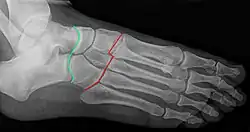

- una articulación del pie, la articulación tarsometatarsiana, conocida como articulación de Lisfranc;

- una lesión traumática de ésta, la fractura-luxación de Lisfranc (clasificada en tres tipos);

- una intervención quirúrgica, la operación de Lisfranc, que consiste en la desarticulación (o amputación) tarsometatarsiana;

- los ligamentos interóseos cuneo-metatarsianos o ligamentos de Lisfranc.